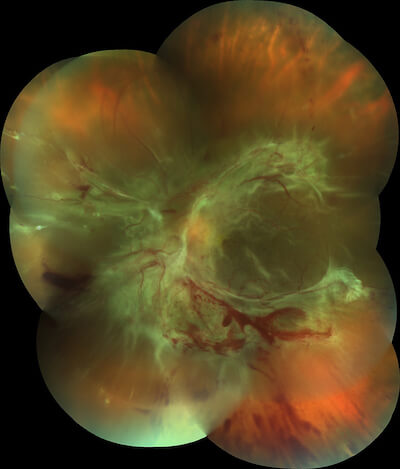

This photo montage illustrates how diabetic retinopathy can affect the retina. Left unchecked, diabetic changes in the retina can lead to scarring, which in turn contracts and may pull on the retina in the back of the eye, resulting in a retinal detachment. This condition requires intensive surgery, and may have been preventable with regular dilated eye exams at the office. If you are a diabetic, be sure to have your eyes checked by an optometrist or ophthalmologist at least once a year.